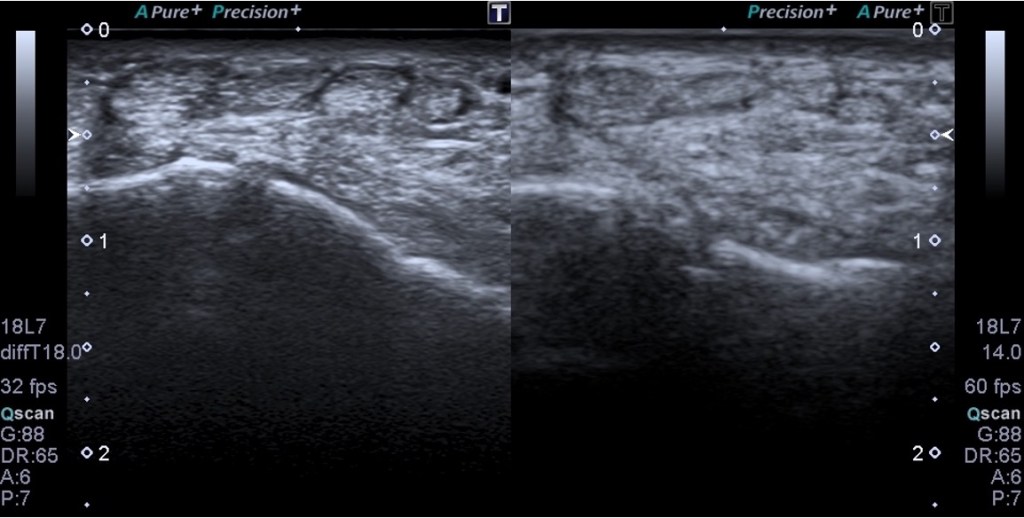

Para implementar esta nueva técnica, es necesario un cambio en la posición del paciente de sedestación a decúbito supino. Este ajuste en la postura es crucial para permitir una visualización óptima del labrum anterior, una región que hasta ahora ha sido difícil de evaluar con precisión.

La exploración comienza colocando el transductor en la posición adecuada para visualizar el tendón del subescapular, similar a la técnica utilizada en sedestación. Luego, se realiza un movimiento pasivo del brazo del paciente, quien debe mantenerlo en flexión y abducción de aproximadamente 90 grados. El operador manipula el brazo para encontrar la mejor visualización del labrum anterior, situado en una posición más profunda.

Valoración de la Articulación Gleno Humeral y la Cápsula Articular Anterior